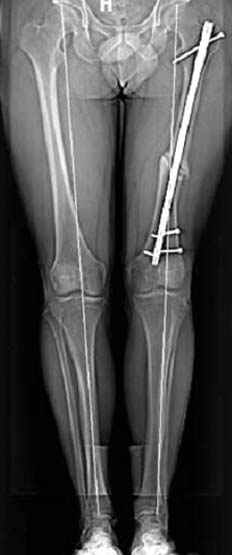

Несколько снимков из моей коллекции, чтобы разьяснить, почему мы до сих пор делаем различные варианты остеотомии.

На рисунке N1 предоперационный план лечения ложного сустава шейки бедра- линия ложного сустава, угол и направление введения импланта, клиновидная остеотомия в градусах и миллиметрах, второй снимок после коррекции, расчет, на сколько удлиняется конечность и размеры импланта;

N3 рисунок окончательный снимок, после операции моя рентгенограмма должен выглядеть примерно как эта картина. На N4 снимке клин перед удалением; N5 послеоперации 3 нед.; N6 окончательная рентгенограмма.

варус при проксимальном отделе 95 градусной пластиной.